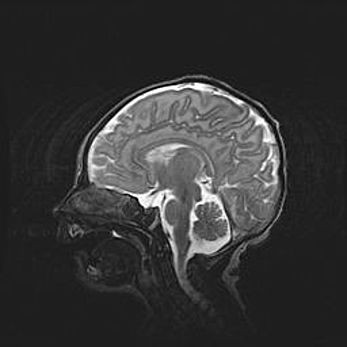

Мальформация Денди-Уокера. Киста задней черепной ямки.

Агенезия мозолистого тела.

Возраст: 2,5 месяца

Вес: 2420 г

Пол: женский

Окружность головы: 37 см

Срок гестации: 32 недели

Мальформация Денди—Уокера — редкий вид патологии ЦНС, представляющий собой врожденный порок развития каудального отдела ствола и червя мозжечка, ведущий к неполному раскрытию срединной (Мажанди) и латеральных (Лушка) апертур IV желудочка мозга. Для этогно синдрома характерна триада симптомов: гипотрофия червя мозжечка и/или полушарий мозжечка, кисты задней черепной ямки, гидроцефалия различной степени. В 70% случаев порок сочетается и с другими аномалиями головного мозга, в частности с агенезией мозолистого тела.